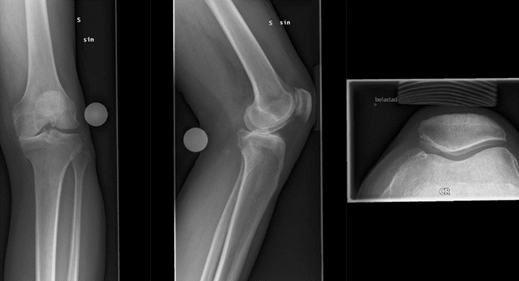

Vad ser du på bilden?

A

• Medial gonartros och från sidan ses oregelbundenheter i den femorala-patellära leden

• Till höger lite pålagringar och liten nabb till höger